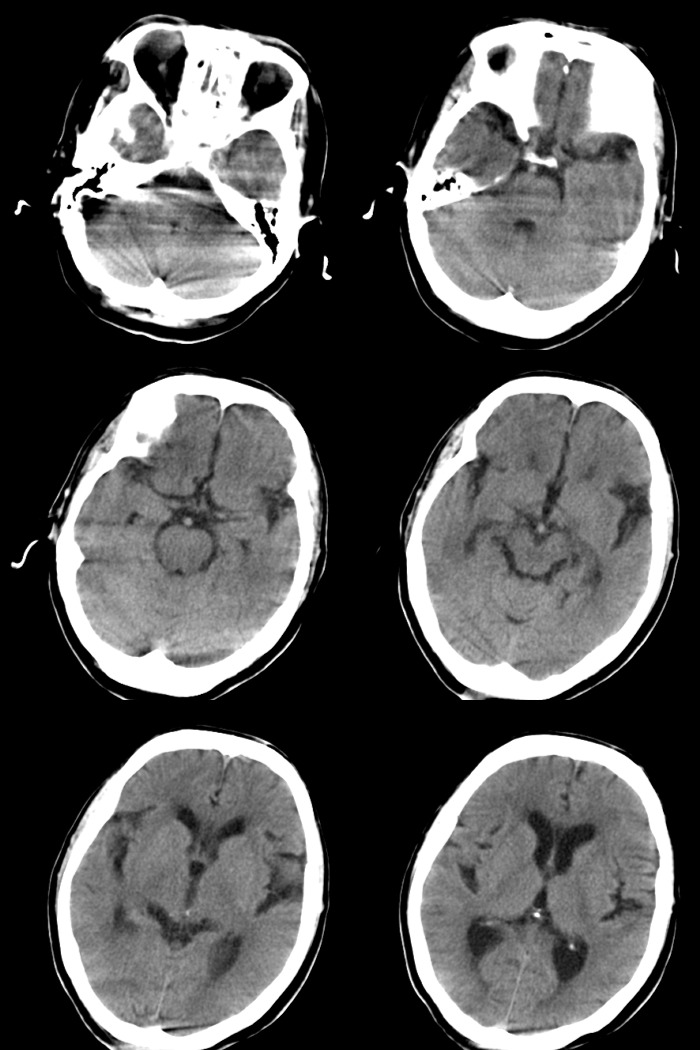

标题: CT17990:F76y,反复头昏。

76岁女性,反复头昏、头痛,余无不适。

诊断:右颞部钙化性脑膜瘤.

诊断依据:1.定位:脑外颅内--邻近脑沟增宽/脑组织受压内移/局部颅骨增生.

2.定性:良性--病灶边缘光整清楚/密度较高均匀/脑组织水肿不明显即占位效应不明显.

鉴别诊断:1.右颞骨内生骨软骨瘤/2.少突胶质细胞瘤/3.弥漫性星型细胞瘤.

1)考虑右颞部钙化性脑膜瘤。2)脑萎缩。

考虑脑膜瘤可能性大,如果是骨软骨瘤应该是广基底与颞骨相连,本例没有发现;当然应该在病灶范围内行薄层扫描进一步查明其与颞骨的关系对诊断有帮助。